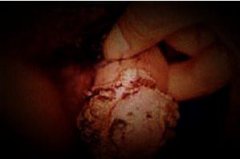

石家庄九州皮肤病医院 > 尖锐湿疣 > > > 得了尖锐湿疣如何治疗能尽快的去疣治愈?尖锐湿疣在临床上不但是严重的损害到患者的生活健康,而且本身也是可以对患者生活产生很大危害的,尤其是尖锐湿疣的传染性是很强的,所以得了尖锐湿疣的患者最好还是能够去科学正规的治疗,而在尖锐湿疣的治疗上患者可以选择的药物方法还是很多的,不过建议患者一定要注意能够彻底的清毒,这是根治尖锐湿疣的重点和关键,只有这样才能让患者得到彻底的根治康复治愈。